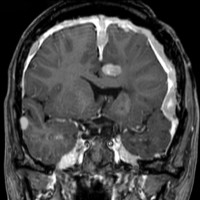

典型的なNF-2の患者さん

中心となるのは神経鞘腫と髄膜腫です。下のMRIは典型的な両側聴神経腫瘍と呼ばれる画像です。両側の内耳道から腫瘍(黒く見えるもの)が突出して,脳幹部を強く圧迫しているために脳幹部が縦長に変形してしまっています。この様にひどい脳幹部変形でもほとんど症状が無く暮らしていた患者さんです。赤い矢印で示すのは横静脈洞内から突出している髄膜腫です。

小脳橋角部腫瘍あるいは聴神経腫瘍と呼ばれるので,左右に一つずつの腫瘍かと思ってしまうのですが,実は違います。この患者さんでは,右側の小脳橋角部腫瘍は,三叉神経鞘腫,前庭神経鞘腫,蝸牛神経鞘腫,顔面神経鞘腫,迷走神経鞘腫,舌咽神経鞘腫,舌下神経鞘腫がすべて一塊になったものでした。ですからこの小脳橋角部腫瘍を摘出しようとすれば,上に書いた神経の麻痺は手術合併症として全部出現する可能性があります。